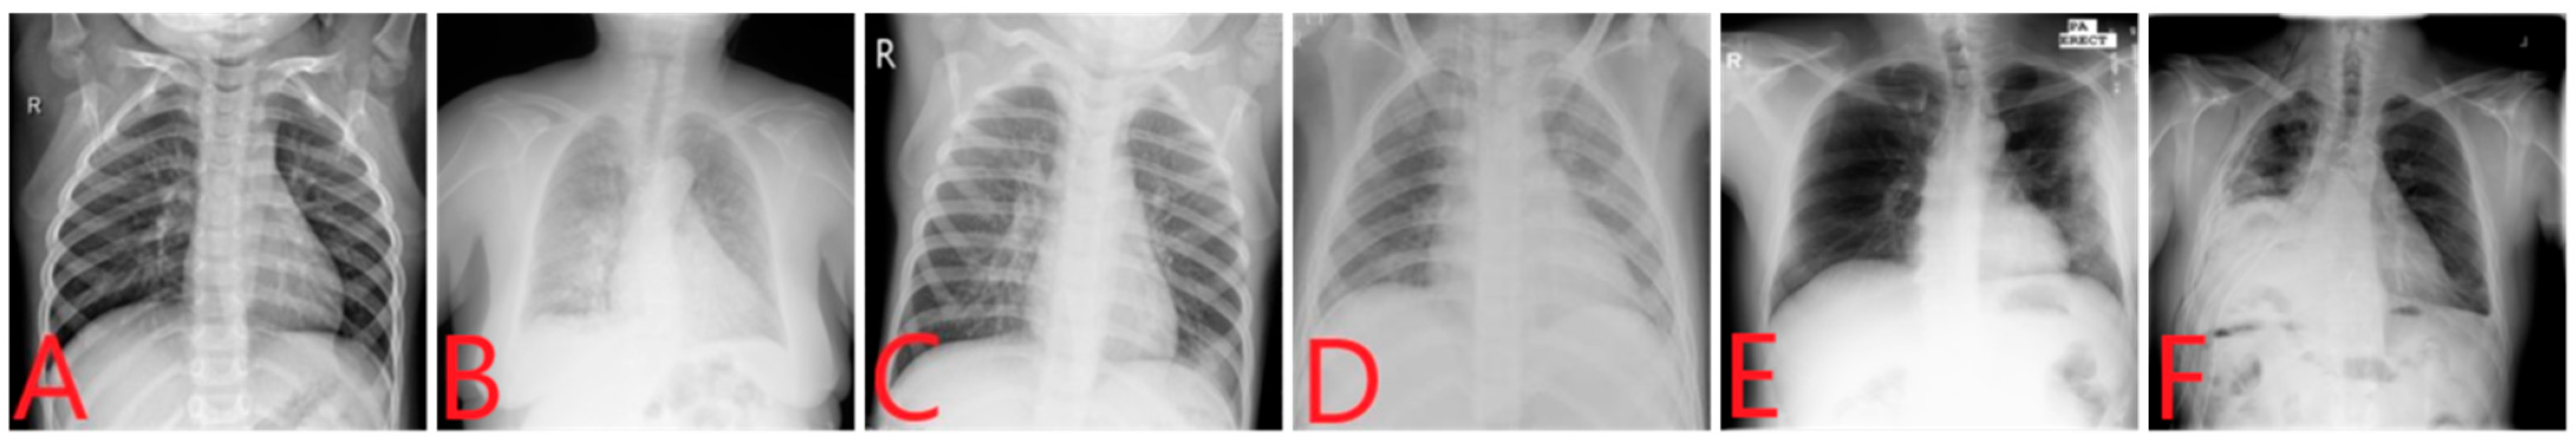

The fourth and last source (https://www.kaggle.com/c/siim-acr-pneumothorax-segmentation, accessed on 25 July 2022) of images was Pneumothorax, which is a collection of 12,047 images, as discussed in [39]. We randomly selected 1200 images of pneumothorax for Dataset-2. For the two-class, three-class, and four-class datasets, we used Dataset-1, and for the six-class dataset, we used Dataset-2. After compiling all images, a balanced four-class dataset was constructed, i.e., Dataset-1, which contained 6000 images and 1500 images for each class including COVID-19, viral pneumonia, Tb, and normal. Then, another balanced dataset was constructed, Dataset-2, which contained 7200 images and 1200 images for each class, including COVID-19, viral pneumonia, bacterial pneumonia, tuberculosis, pneumothorax, and normal. Both datasets contained more images than those used in previous studies [4,20,24,40]. Figure 1 shows samples of X-ray images used in this study. These images are (A) Normal, (B) COVID-19, (C) Viral pneumonia (D) Bacterial pneumonia (E) Tb, and (F) Pneumothorax.

Figure 1.

Sample images of different diseases: (A) Normal, (B) COVID-19, (C) Viral pneumonia, (D) Bacterial pneumonia, (E) Tb, and (F) Pneumothorax.